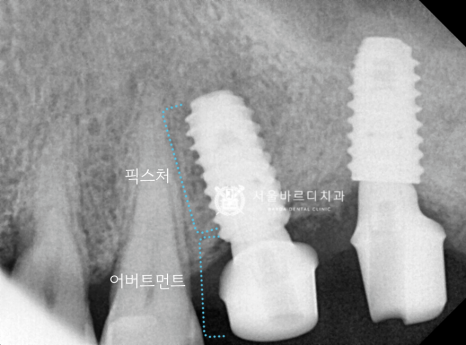

임플란트의 뿌리 역할을 하는

픽스처를 넣기 위해서 충분한 폭이 필요한데

가이드 장치를 끼운 상태에서

해당 부위만 길을 만들어서 픽스처를 심은 덕분에

하치조 신경관의 손상 없이 바르게 심겼네요.

스캐너로 픽스처와 잇몸의 위치를 기록한 덕분에

맞춤 기둥을 잘 맞게 만들어 올 수 있었고,

기둥을 체결한 다음 보철을 올려서 확인해 보니

맞물림도 잘 맞아서 바로 붙여드릴 수 있었습니다.